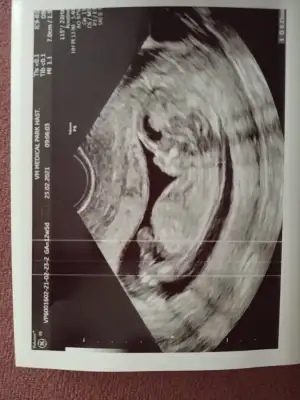

Kızlar Merhaba, bugün 12+5 ve ikili tarama için ultrason yapıldı. CRL 6.6 haftası ile uyumluymuş ancak ense kalınlığı 2.3 çıktı. Doktorum sınırın 2.5 olduğunu ve sınıra yakın olduğu için Down Sendromu riski içerdiğini söyledi. Nipt önerdi ancak bunun için kan tahlilinin de sonucunu bekliyorum. 26 yaşıma yeni girdim, hep sağlıklı beslenirim, alkol ve sigara kullanmıyorum. Yani risk grubunda değilim bu yüzden telaşlıda değilim ama yine de moralim bozuldu. Benzeri bir durum ile karşılaşan oldu mu?